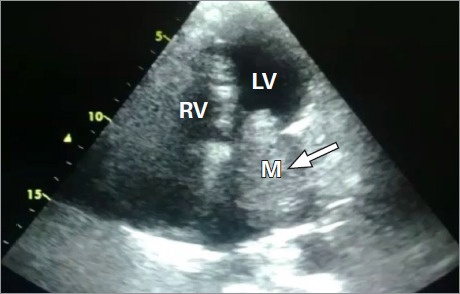

Rhabdomyosarcoma represents almost 20% of all primary malignant neoplasms of the heart. In the majority of cases, the tumor arises from the ventricular wall, although these tumors can also arise from the atrial walls and mimic atrioventricular valve stenosis. This report presents a case of a patient diagnosed with an atrial mass that was detected by transthoracic echocardiography and confirmed by histopathology. The mass was successfully resected during an uneventful surgical intervention, but the patient died 6 months after the procedure.